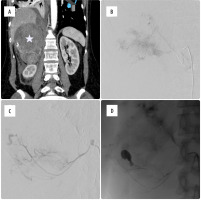

All procedures were carried out by an experienced interventional radiologist under local anaesthesia or conscious sedation from femoral access. Firstly, an aortic angiography from a 5 Fr diagnostic catheter positioned above the renal level was performed. Afterwards, possible culprit vessels (phrenic, renal, and adrenal arteries) were selectively catheterised and investigated. If signs of vessel injury (contrast extravasation, abnormal blush) were detected superselective catheterisation with a 2.7 Fr microcatheter was performed. Embolic agents were adopted according to the type of vessel lesion and operator’s preference. Control DSA was performed to confirm vessel occlusion. The puncture site was compressed or closed with a closure device. The typical endovascular procedure is presented in Figure 1.

Figure 1

Embolisation procedure in a 67-year-old male patient with metastatic lesion in a right adrenal gland originating from lung cancer with signs of haemodynamic instability due to haemorrhage. A) Baseline contrast-enhanced CT disclosed large right-sided lesion in an adrenal gland (white star) with visible contrast extravasation in the lower part. Intraprocedural contrast injection showed extraluminal blush (B), and signs of contrast extravasation (C) suggestive of active bleeding from upper and middle adrenal arteries. D) Control imaging obtained after embolisation with glue showed successful exclusion of the culprit vessels